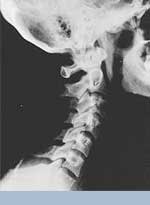

Phase One Subluxation Degeneration is seen in subluxations that have been present for up to twenty years. This phase is characterized with a loss or change in the normal curve in the spine. On this example you can see that the normal forward (lordotic) curve is lost. This spine even has developed a reverse curve in the neck. The disc spaces have also begun to exhibit a slight change in shape. One good point is that the bodies of each of the vertebrae (the square part in front) still exhibits clean clear borders. Segmental motion may be abnormal but overall motion is probably not affected. Chiropractic reconstructive care for a phase one can take from 6 to 18 months. More than 80% of people with Phase One Subluxation Degeneration have no pain. Therefore, if left uncorrected, phase one continues to progress with time until it eventually reaches the next phase.